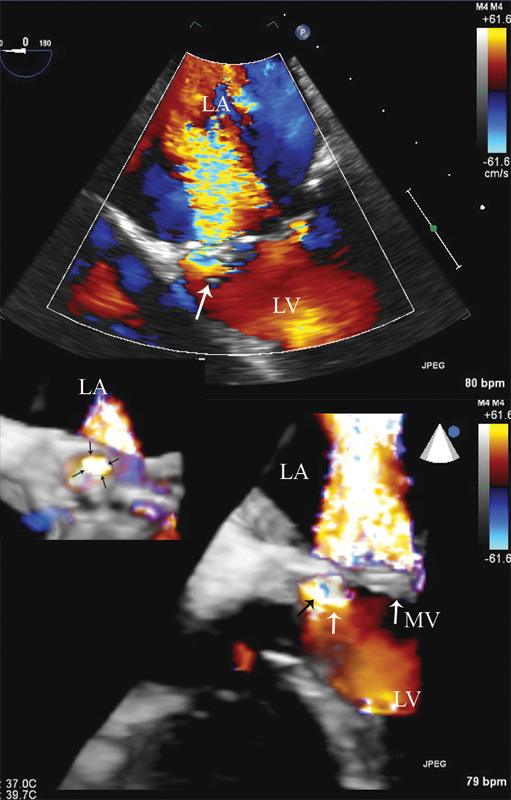

فحوصات تشخيصية لبعض امراض القلب والشرايين التاجية